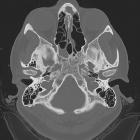

arrested pneumatization of skull base

CT

Characteristic features on CT are the presence of:

- a non-expansile lesion with

- internal curvilinear calcifications and

- sclerotic margins